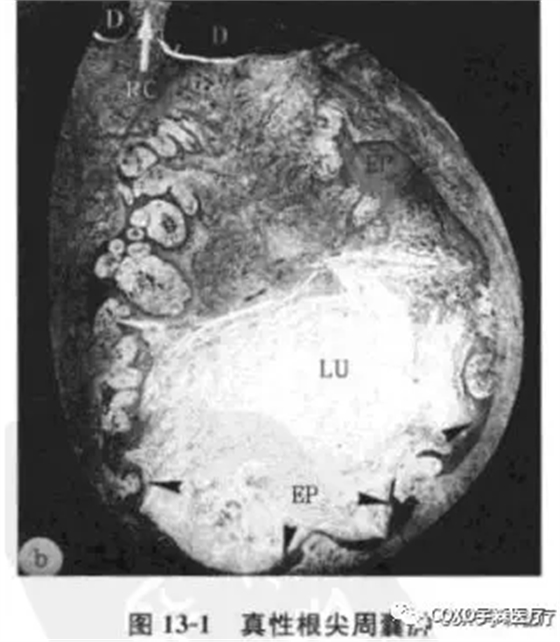

真性根尖周囊腫:包括4個主要成分:

①囊腔;

②囊壁上皮;

③上皮外組織;

④外周環(huán)形排列的膠原纖維。囊腔完全由上皮層包裹與根管隔離,腔內(nèi)一般含有壞死組織,偶爾含有膽固醇晶體。紅細(xì)胞和中性粒細(xì)胞主要存在于上皮層內(nèi)(圖13-1)